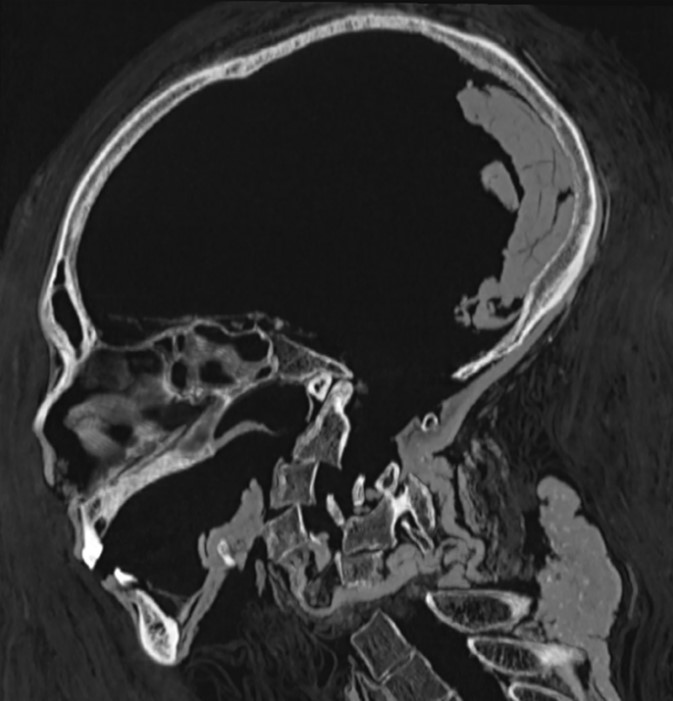

Ảnh chụp CT xác ướp 3,500 năm tuổi của Pharaoh Amenhotep I.

Hình ảnh chụp CT ba chiều phần đầu của xác ướp [pharaoh] Amenhotep I. (Ảnh: Đăng dưới sự cho phép của Sahar N. Saleem và Zahi Hawass)

Hình ảnh CT ba chiều kỹ thuật số của khuôn mặt không được bao phủ của xác ướp [pharaoh] Amenhotep I. (Ảnh: Đăng dưới sự cho phép của Sahar N. Saleem và Zahi Hawass)

Xác ướp của [pharaoh] Amenhotep I được mô tả là có khuôn mặt trái xoan với đôi mắt trũng sâu và hai má hóp lại. Ông có phần mũi nhỏ, hẹp và tẹt, hàm răng hơi đưa ra ngoài. Ông cũng có đôi tai nhỏ với một chiếc khuyên nhỏ ở dái tai trái. Đáng chú ý là ông được phát hiện có một vài lọn tóc cuộn ở phía sau và hai bên đầu.

Các ước tính trước đây về tuổi của [pharaoh] Amenhotep I được thực hiện dựa trên phương pháp khám nghiệm bằng X-quang lần đầu tiên vào năm 1932 đã phát hiện ông [băng hà] trong khoảng từ 40 đến 50 tuổi. Sau đó vào năm 1967, bằng phương pháp phân tích răng, [các nhà khoa học đã định ra] ông qua đời ở năm 25 tuổi. Tuy nhiên, trong các lần chụp CT gần đây, [các nhà khoa học đã] quan sát tại phần khớp dính xương mu (phần xương ở phần xương chậu dưới trở nên nhẵn dần theo tuổi tác), đã định ra rằng ông qua đời ở tuổi 35.